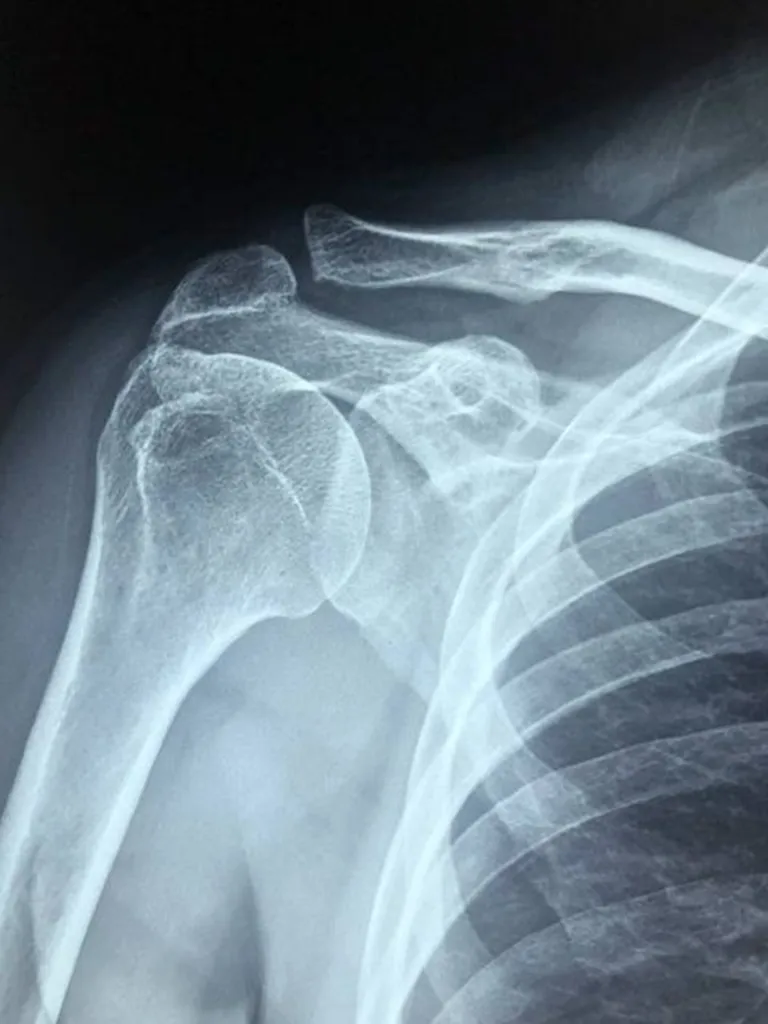

16.200 € accordés par le tribunal correctionnel de Marseille à une victime de vol avec agression corporelle ayant subi un traumatisme cervical et un choc psychologique

Par jugement du 15 décembre 2023, le tribunal correctionnel de Marseille a condamné l'auteur d'un vol avec agression, à verser à la victime, la somme de 16.200 € à titre de dommages et intérêts en réparation de son préjudice corporel.Les postes de préjudices corporels indemnisés les plus important...